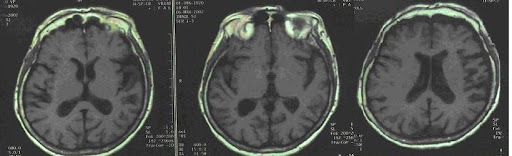

Retinadaki sinir lifi tabakasının kalınlığı daha önce bilişsel performansla ilişkilendirilmişti. Bu çalışmada da sinir lifleri, ganglion hücreleri ve iç pleksiform tabakası mercek altına alındı. Özellikle sinir lifi tabakası önemliydi çünkü görsel sinyalleri beyne taşıyan lifleri içeriyordu.

Ancak bu kez, araştırmacılar retinal mikrodamar sağlığının demans riskiyle daha güçlü bir ilişki gösterdiğini fark etti. Retinada bulunan küçük atardamarların (arteriyoller) daralması ve küçük toplardamarların (venüller) genişlemesi, demans riskinin artışıyla bağlantılı bulundu.

Bu damar yapıları, yalnızca göz sağlığı değil, vücudun genel damar sistemi ve özellikle beyin damar sağlığı hakkında da bilgi sunuyor. Alzheimer’ın gelişiminde damarsal etkenlerin önemli bir rol oynadığı biliniyor.